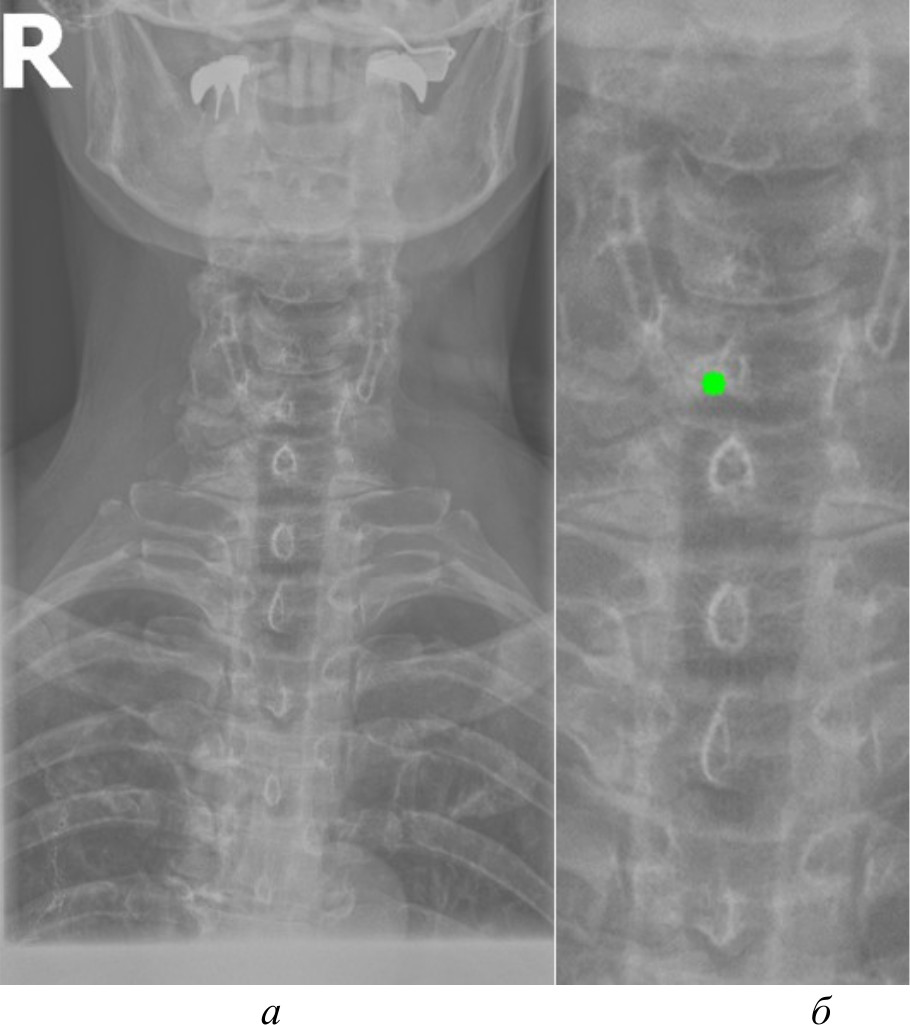

Автоматизированное распознавание таких ключевых анатомических ориентиров на рентгеновских изображениях представляет собой важную задачу, решение которой может повысить точность и скорость медицинской диагностики, обеспечив врачей объективной информацией для принятия решений. Компьютерное зрение способно автоматически локализовывать и идентифицировать анатомические структуры, измерять их размеры и взаимное расположение, а также выявлять отклонения от нормы, указывающие на наличие патологий. Однако недостаточное качество рентгеновских снимков, наличие помех, артефактов и неравномерностей может затруднять их восприятие системами компьютерного зрения. На рис. 1, а продемонстрирован рентгеновский снимок без предварительной обработки.

Рис. 1. Рентгеновский снимок без предварительной обработки (а); результаты работы детектора Harris на изображении без предварительной обработки (б)

Как видно на рис. 1, б, применение алгоритмов компьютерного зрения на необработанном изображении приводит к нечетким и неустойчивым результатам обнаружения ключевых анатомических ориентиров. Тем самым важной задачей, обеспечивающей эффективное применение алгоритмов компьютерного зрения, является разработка эффективных алгоритмов предварительной обработки изображений. Данные предварительной обработки, такие как улучшение контраста и устранение артефактов, служат основой для более точного и надежного анализа с использованием алгоритмов компьютерного зрения. Это позволяет повысить качество обнаружения ключевых анатомических ориентиров, играющих критическую роль в идентификации и оценке патологических изменений.